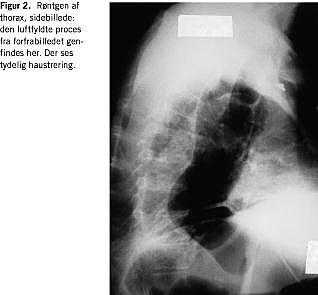

Blodtrykket var 220/120. Et elektrokardiogram (ekg) viste sinustakykardi, frekvens 134, uden tegn på iskæmi. Patientens saturation ved ankomsten var 92% på 8 l ilt pr. min. A-punktur viste svær respiratorisk acidose, pH=7,13. Røntgen af thorax viste en dilateret subdiafragmalt beliggende ventrikel og en dilateret colonslynge i mediastinum strækkende sig helt op i halsregionen, der sås normale lungefelter (Figur 1 og Figur 2 ).

I den foreliggende sygehistorie har der formodentlig været tale om herniering gennem hiatus oesophageus. Dette blev vurderet af en speciallæge i radiologi ud fra røntgen af thorax i to planer.